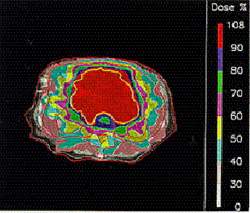

| Облучение g-квантами | Облучение протонами |

| Вид лучевой терапии |

Локализация дозы | Лечению поддаются | |

| протоны | отличная | + | - |

| нейтроны | плохая | + | + |

| ядра 12C | отличная | + | + |